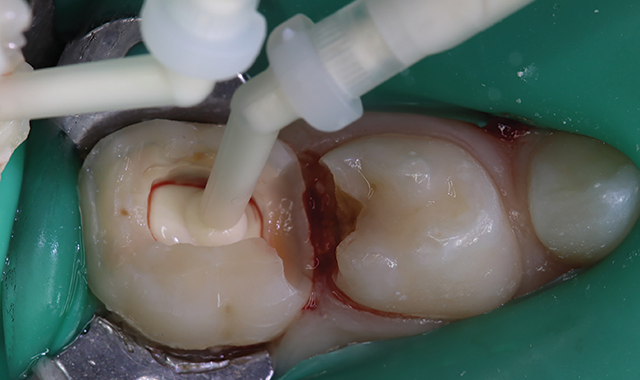

Pre-operative view shown in Figure 1. Primary second molar requiring pulpotomy procedure.

Fig. 1.

Amputation of coronal pulp chamber to the level of radicular pulp stumps was performed with NSK Dental slow speed large round bur #8, removing coronal pulp tissue with gentle upward motion (Fig. 2). Hemostasis is achieved with a saline-soaked sterile cotton pellet (Figs. 3-4). Figure 5 also illustrates hemostasis.

[ Figs. 1-9 ] Pre-operative view-primary second molar requiring pulpotomy procedure (Fig. 1). Amputation of coronal pulp chamber to level of radicular pulp stumps with NSK Dental’s slow speed large round bur #8, removing coronal pulp tissue with gentle upward motion (Fig. 2). Hemostasis achieved with saline-soaked sterile cotton pellet (Figs. 3 & 4). Hemostasis achieved (Fig. 5). Extrusion of TheraCal PT into pulp chamber, being sure to reach base of coronal pulp chamber with material and without voids or bubbles and light cure (Figs. 6 & 7). Cured TheraCal PT (Fig. 8). Full-coverage stainless-steel crown (Fig. 9).